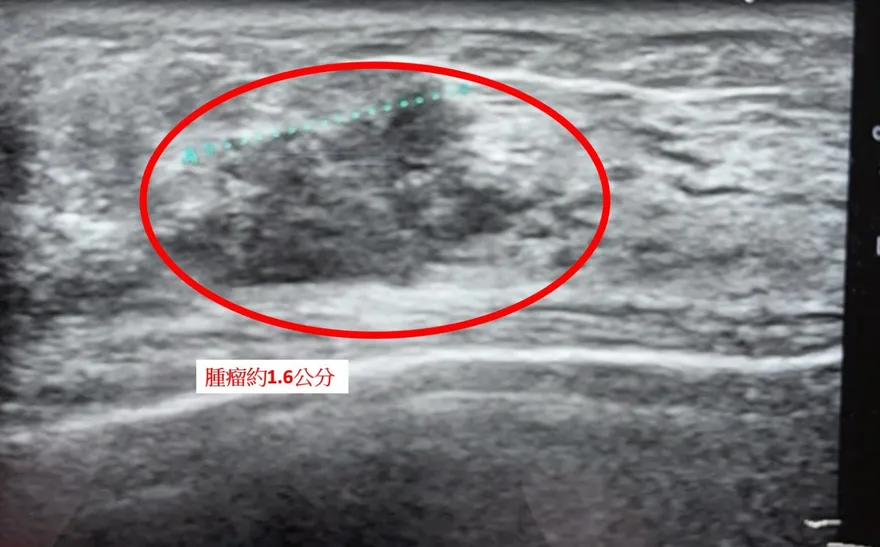

他鎖骨上「摸到硬硬的」淋巴結 !就醫竟罹肺癌 腫瘤已長到5cm大

肺癌

蘇一峰

癌細胞

癌症擴散

肺部腫瘤

淋巴結

鎖骨

脖子